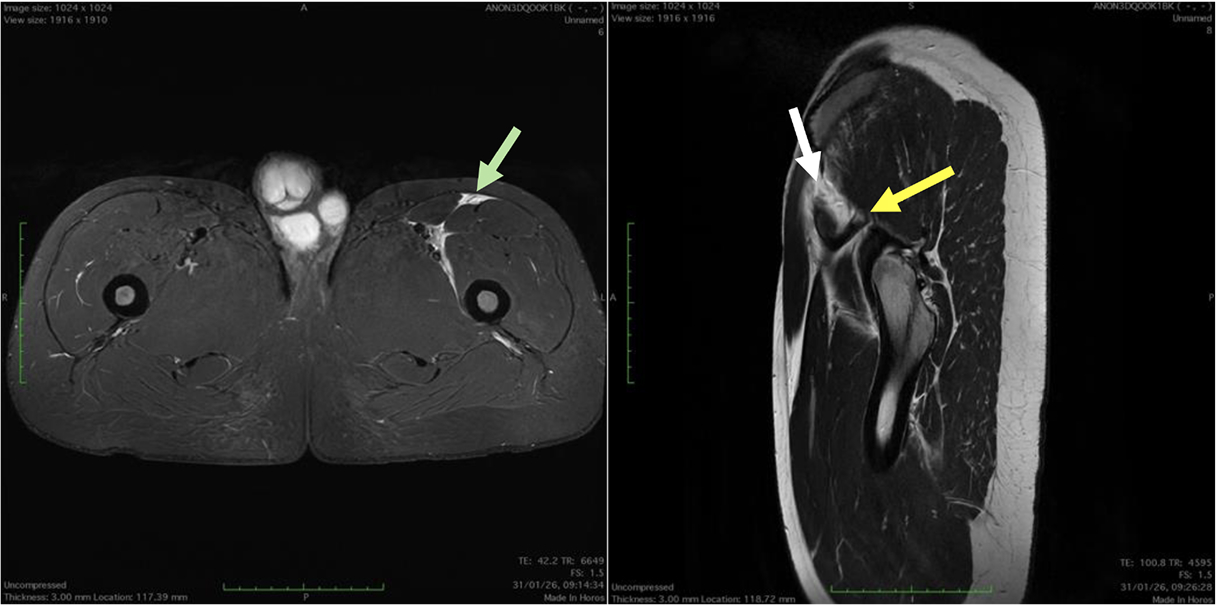

Fifty shades of grey

Caso condiviso da Marcello De Santis